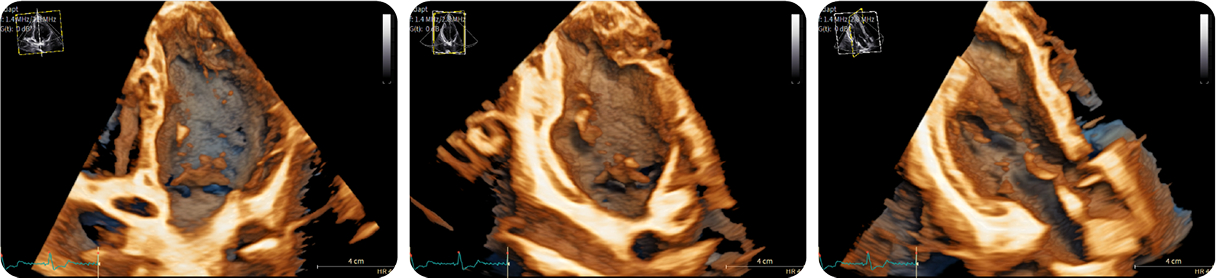

Casi clinici

Scopri come le tecnologie di imaging più innovative di GE HealthCare hanno giocato un ruolo chiave nella diagnosi di condizioni cardiache complesse.